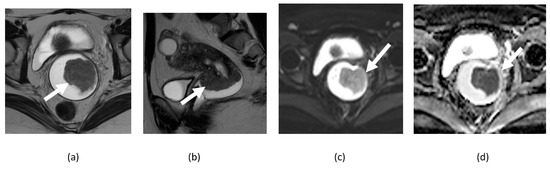

3.5. Mature Cystic Teratoma